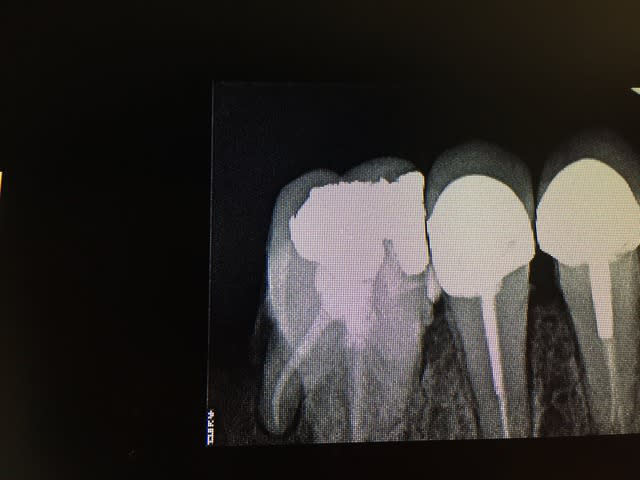

Après je suis pas aussi bon que toi en endo mais il m'arrive de ne pas faire que de la merde :D (d'ailleur on peut voir que le collage ça merde aussi :D)

Img 0149 oenlvw - Eugenol

Img 0080 s1bzju - Eugenol

Img 0148 nvqa6d - Eugenol

Img 0081 yyn6kb - Eugenol

Img 0128 xjeo9i - Eugenol

Img 0129 l72nv1 - Eugenol